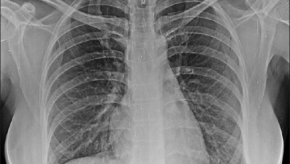

Psoriatic Arthritis at Risk for Interstitial Lung Disease

A TriNetX EHR study shows that psoriatic arthritis, but not psoriasis, patients are at increased risk for interstitial lung disease (ILD).